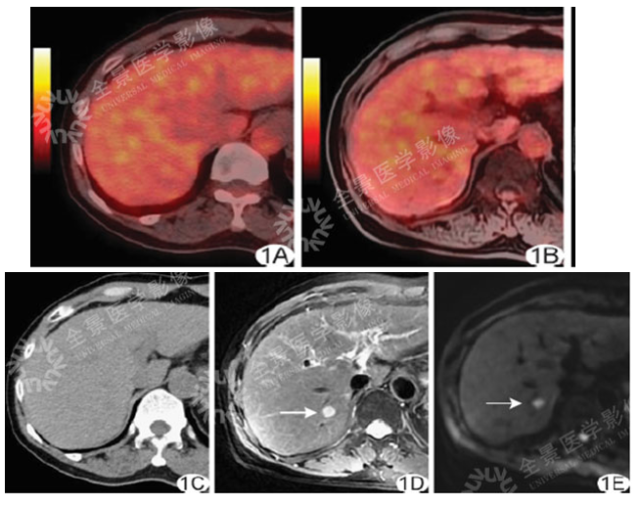

男 50 岁 小肝癌:

案例一